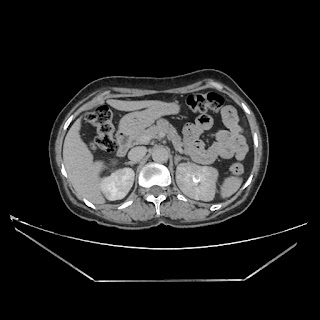

Urography images

A 50 years old woman with suffering from left sided PUJ obstruction